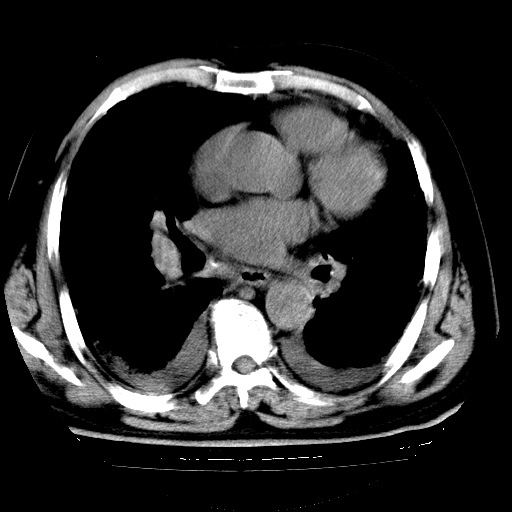

男,68岁,咳嗽、胸闷、发烧三天,查体:双肺散在湿罗音。

1.双肺间质纤维化并感染;

4.肺原性心脏病;

5.双侧胸腔少量积液;双侧胸膜增厚。

慢支合并感染.间质纤维化,心衰双侧少量胸腔积液

支持 慢支合并感染.间质纤维化,心衰双侧少量胸腔积液.

两肺广泛条索状、网格状、蜂窝状改变。肺间质纤维化,肺心病,双侧胸腔积液